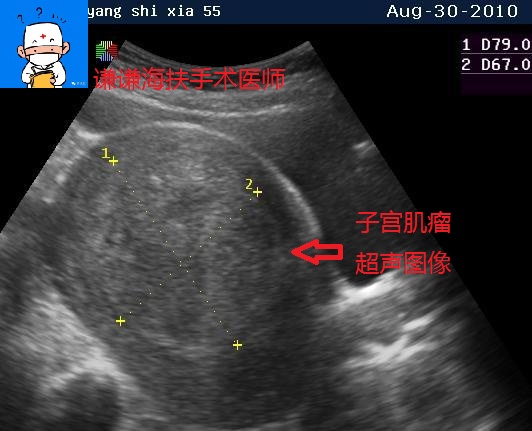

首先我们看看正常的子宫肌瘤超声和磁共振图像